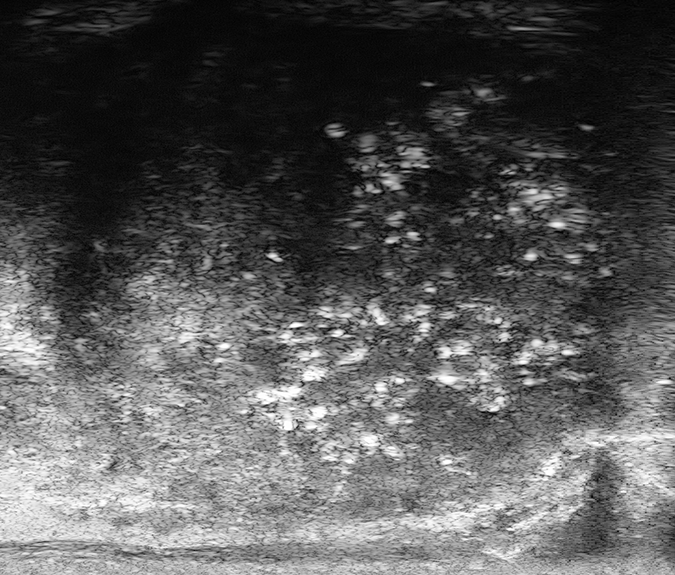

PRI-MUS 4

Heterogeneous “Cauliflower”, “smudgy or mottled” or Bright Echoes (”Starry Sky”)